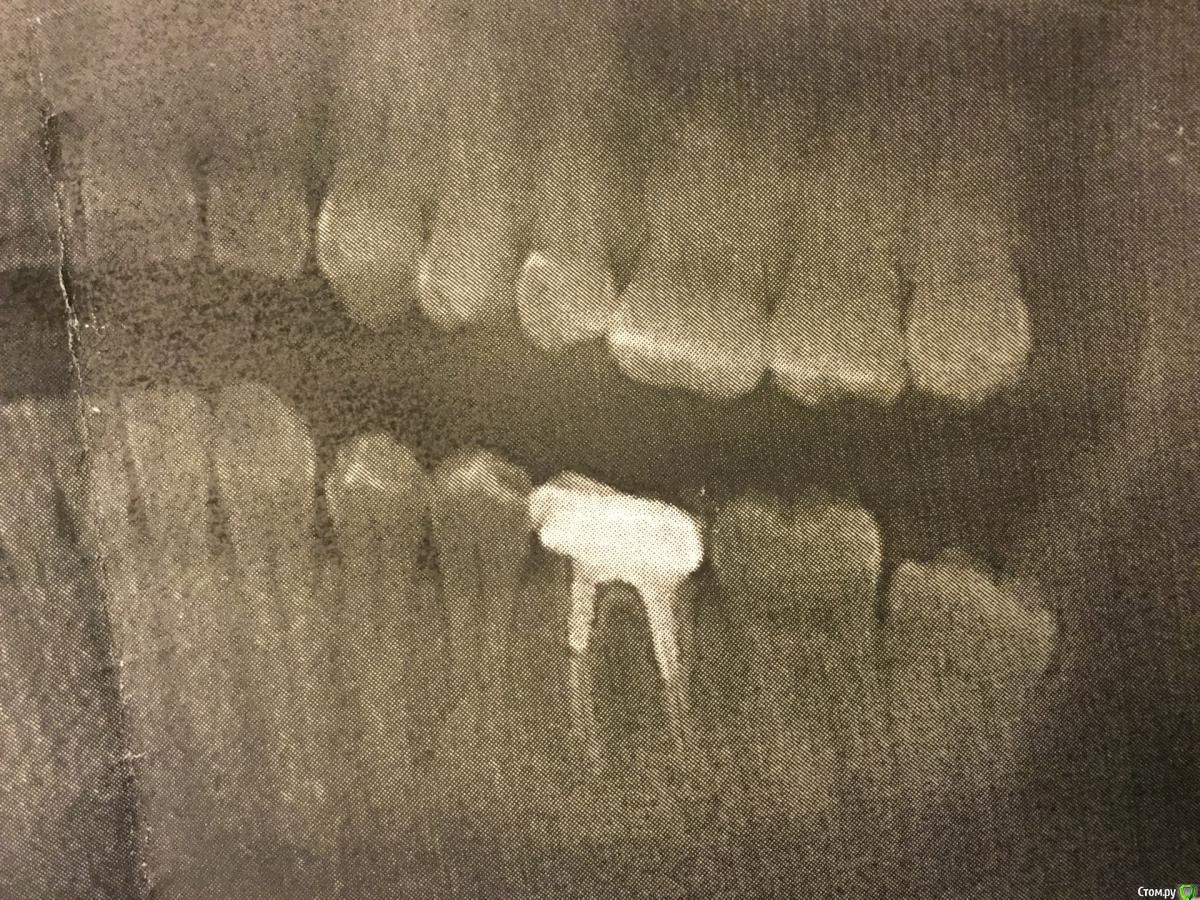

TR909 Опубликовано 19 декабря, 2018 Поделиться Опубликовано 19 декабря, 2018 Здравствуйте, Товарищи! Прошу помочь советом.Есть у меня многострадальный зуб, который лечили, потом перелечивали, потом пломбировали каналы, потом перепломбировывали, нахлобучили всю эту прелесть коронкой и я был абсолютно счастлив лет 7. Периодически распухала десна и даже как-то шел гной, но это всю фигня в масштабах вселенной, думал я. И вот опять десна распухла, а потом и часть челюсти толи онемела, толи как-будто там что-то чужеродное стало ощущаться и я, не долго думая, пошел к хорошему хирургу, сделали 3д рентген и обнаружили гной у корней моего многострадального зуба, причем вроде как немало гноя. Хороший хирург однозначно сказал, надо выдирать и ставить имплант (он не только хороший хирург, но и хороший имплантолог и вообще замечательный человек). А мне так жалко этот зубик с которым мы вместе так много прошли и вот сижу я и думаюю что с ним делать: попробовать еще раз вылечить или выдрать и забыть.Подсобите советом: лечит ли кто в Москве такие зубы, с запломбированными каналами, коронкой, гноем под корнями и свищом на десне и насколько вообще реально его вылечить? Или удалить нафиг и походить пока с дырой покопить деньги на имплант? Ссылка на комментарий

TR909 Опубликовано 19 декабря, 2018 Автор Поделиться Опубликовано 19 декабря, 2018 (изменено) Левая нижняя шестерка Изменено 19 декабря, 2018 пользователем TR909 Ссылка на комментарий

DmitrySH Опубликовано 19 декабря, 2018 Поделиться Опубликовано 19 декабря, 2018 Данный снимок невозможно интерпретировать в виду отсутствия четкости. Лучше всего переделать на визиографе 3 Ссылка на комментарий